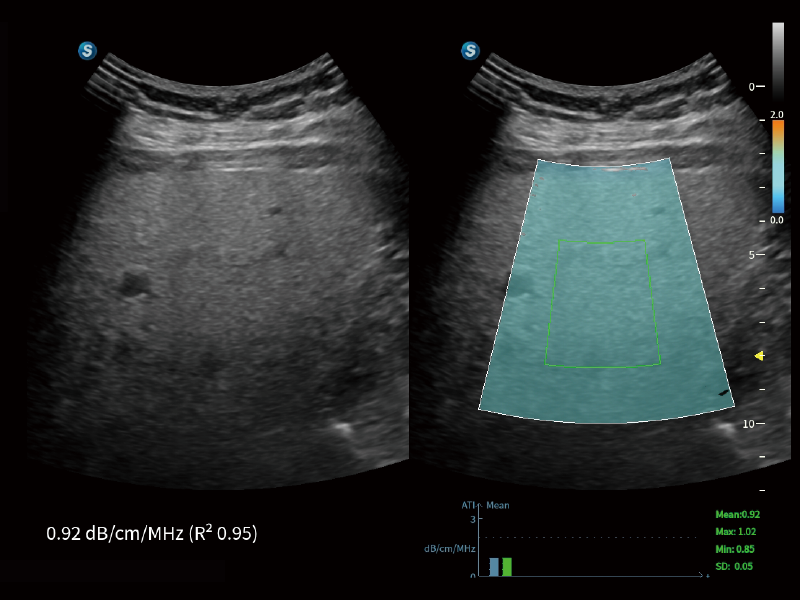

S80 提供多樣化超聲成像技術(shù),可滿足不同科室的需求,在助力掃查診斷和介入治療中發(fā)揮著重要作用。